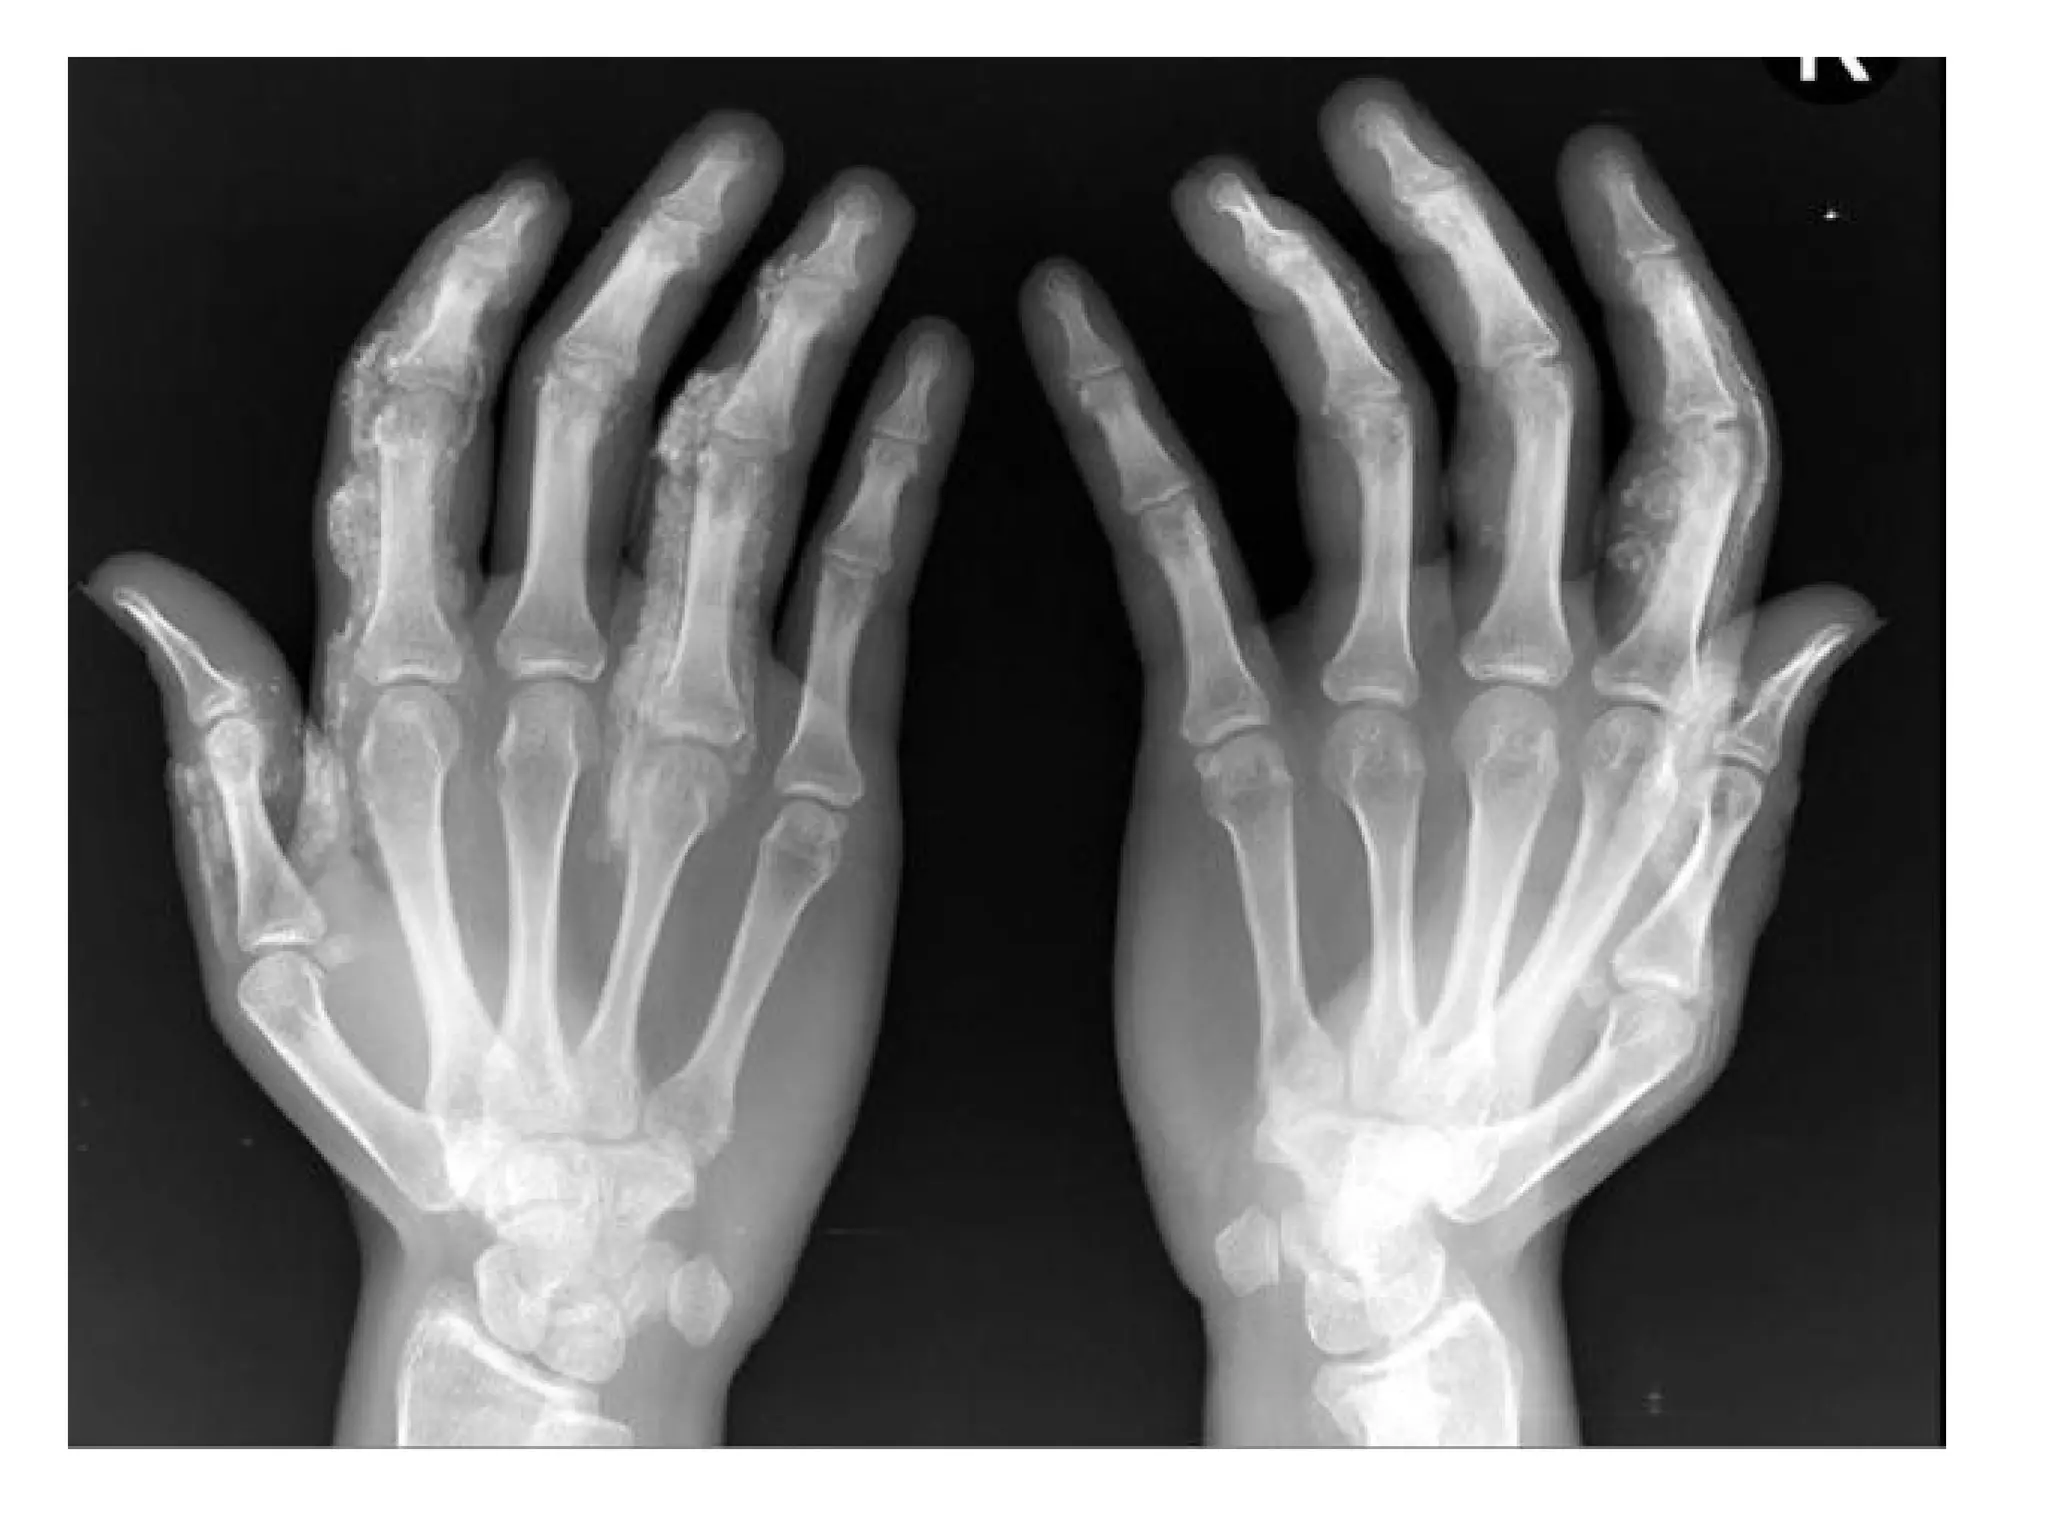

Advanced changes of rheumatoid arthritis with soft tissue swelling (yellow

arrows) , narrowing of the radiocarpal joint space (blue arrow) , erosions

(red arrows) and destruction of the ulnar styloid (green arrow) , the

intercarpal joints are destroyed as re all of the carpal-metacarpal joints of

both hands , note the symmetric appearance of the disease